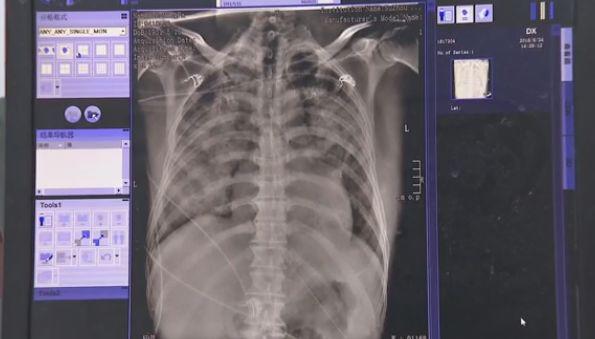

Theo tìm hiểu của bác sĩ, người bệnh là ông Lưu, 50 tuổi. Sau khi kiểm tra cho ông Lưu, bác sĩ phát hiện, bệnh nhân có nhiều cơ quan bị suy yếu, các chỉ số gan, thận có những bất thường nghiêm trọng, đến ngày thứ hai sau khi nhập viện ông Lưu đã tử vong. Cả 2 lá phổi đều đã bị bạc trắng vì phù phổi, lượng lớn chất lỏng đã thấm vào phổi, dẫn đến suy hô hấp.